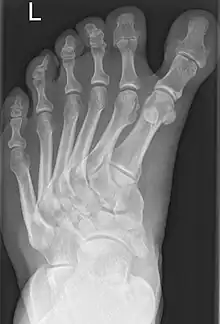

Polydactyly-associated polymetatarsia. | |

Polymetatarsia is a rare congenital malformation which is characterized by the presence of 6 or more metatarsal bones in the same foot. It is most commonly seen alongside polydactyly,[1] and it often appears between the fourth and fifth metatarsals or beside the fifth metatarsal.